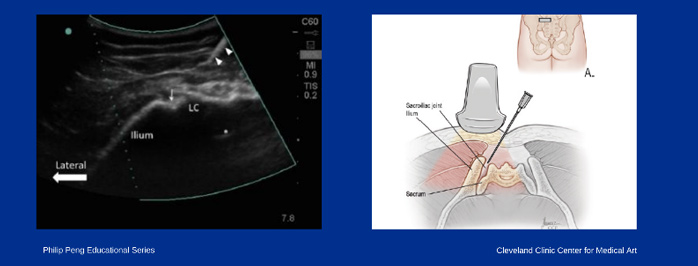

Bloqueio da Articulação Sacroilíaca

A articulação sacroilíaca é uma grande articulação localizada ente sacro e o ilíaco (osso da bacia), sendo responsável pela ligação da parte inferior da coluna vertebral com a pelve. O comprometimento desta estrutura é causa comum de dor lombar crônica, e deve sempre ser pesquisada.

A dor é localizada na maioria das vezes na região glútea, mas também é frequente ocorrer na região lombar baixa. Em alguns casos pode se estender para virilha e membros inferiores.O diagnóstico é feito pelo exame clínico e pode ser auxiliado por exames complementares, mas o diagnóstico deve ser confirmado por um bloqueio diagnóstico.

O bloqueio teste é realizado colocando anestésico local na articulação suspeita, confirmando assim o diagnóstico. Este procedimento deve ser sempre realizado guiado por imagem (ultrassom ou radioscopia) para garantir um resultado fidedigno.

O tratamento para dor sacro ilíaca inclui o uso de medicamentos, terapia física especializada, acupuntura. Os procedimentos intervencionistas, tem um papel importante, podendo usar infiltrações articulares com anestésicos, anti-inflamatórios, ácido hialurônico e medicina regenerativa e em alguns casos a denervação desta articulação.

Soneji N, Bhatia A, Seib R, Tumber P, Dissanayake M, Peng PW. Comparison of Fluoroscopy and Ultrasound Guidance for Sacroiliac Joint Injection in Patients with Chronic Low Back Pain. Pain Pract. 2016;16(5):537-544. doi:10.1111/papr.12304